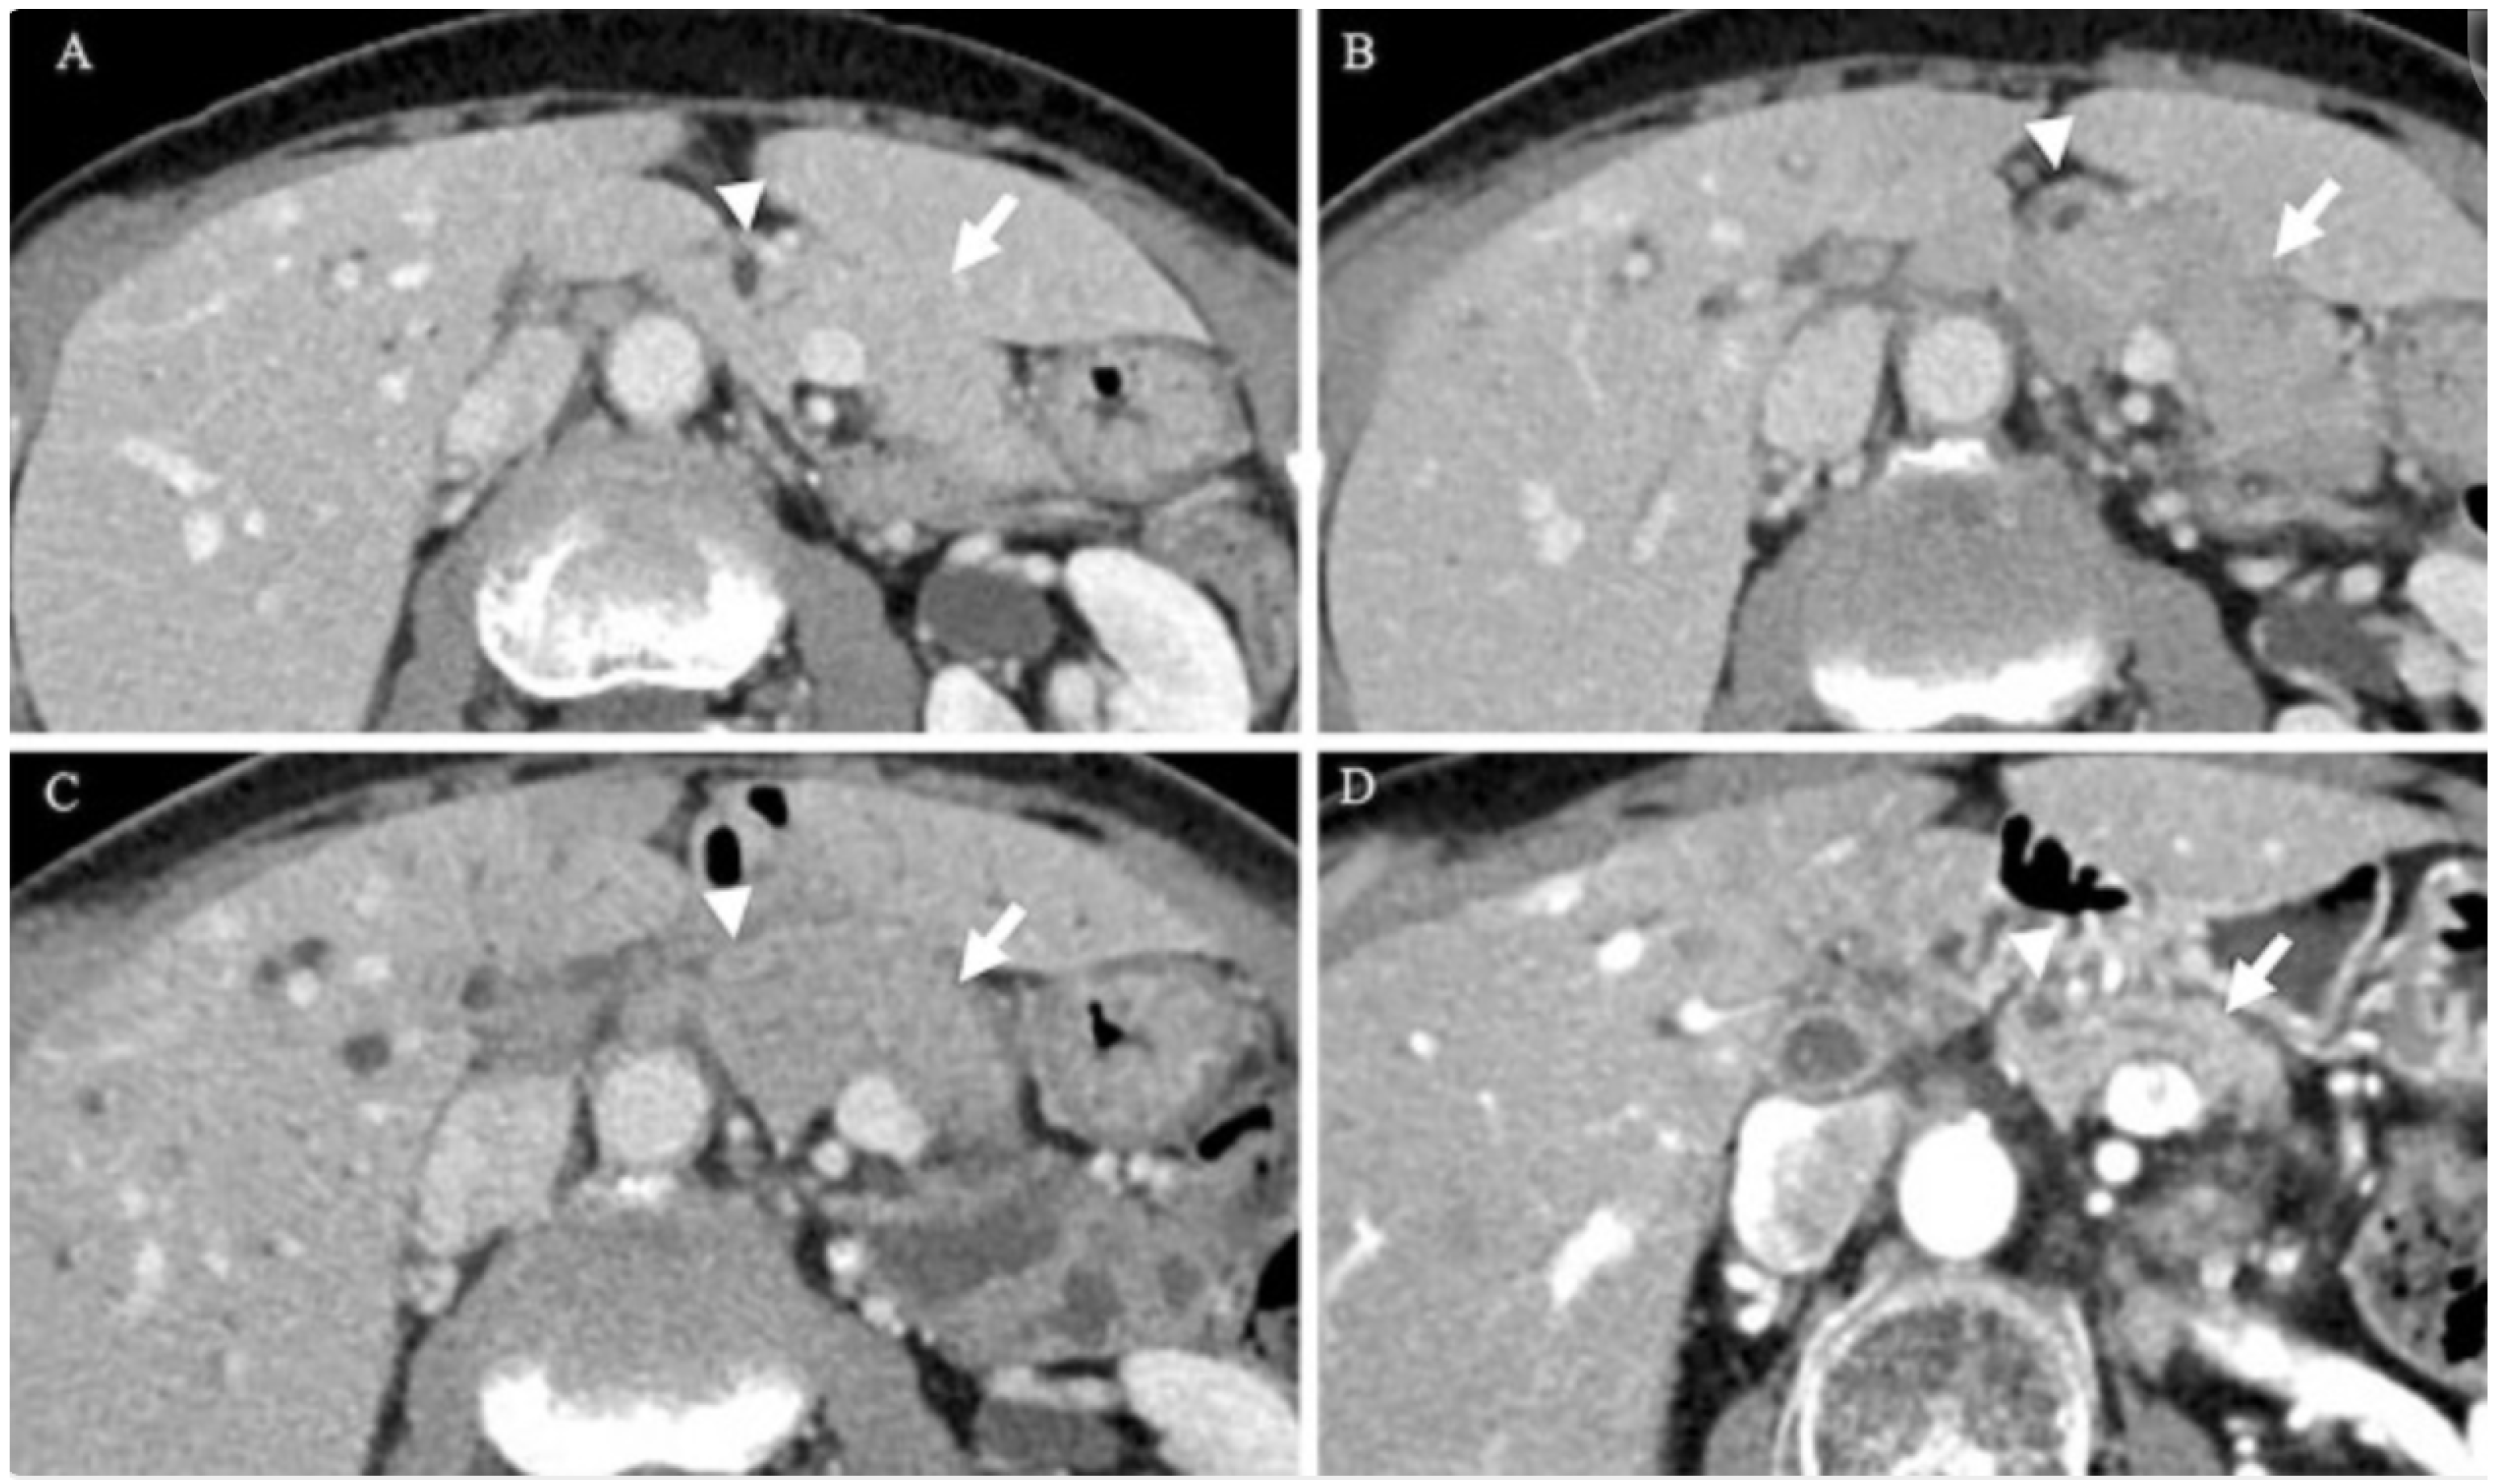

5.1. Radiographic Findings

- Rehnitz, C.; Klauss, M.; Singer, R.; Ehehalt, R.; Werner, J.; Büchler, M.W.; Kauczor, H.-U.; Grenacher, L. Morphologic patterns of autoimmune pancreatitis in CT and MRI. Pancreatology 2011, 11, 240–251. [Google Scholar] [CrossRef]

- Lee, S.; Kim, J.H.; Kim, S.Y.; Byun, J.H.; Kim, H.J.; Kim, M.-H.; Lee, M.-G.; Lee, S.S. Comparison of diagnostic performance between CT and MRI in differentiating non-diffuse-type autoimmune pancreatitis from pancreatic ductal adenocarcinoma. Eur. Radiol. 2018, 28, 5267–5274. [Google Scholar] [CrossRef]

- O’Reilly, D.A.; Malde, D.J.; Duncan, T.; Rao, M.; Filobbos, R. Review of the diagnosis, classification and management of autoimmune pancreatitis. World J. Gastrointest. Pathophysiol. 2014, 5, 71–81. [Google Scholar] [CrossRef]